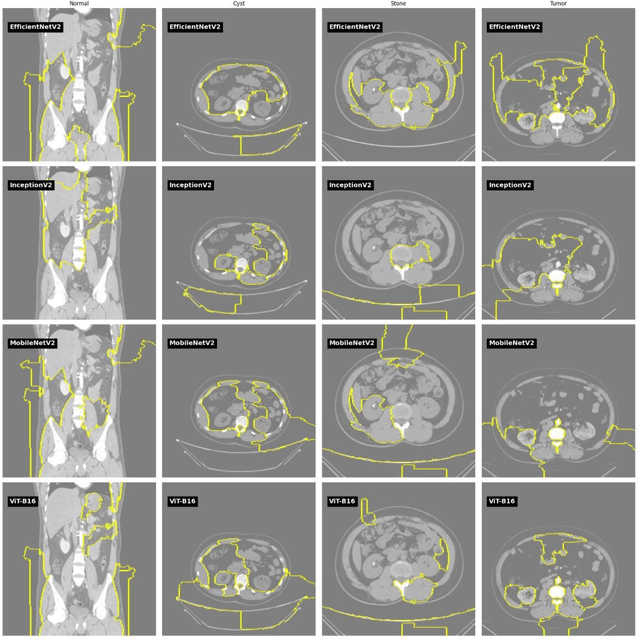

Abstract:Chronic Kidney Disease (CKD) represents a significant global health challenge, characterized by the progressive decline in renal function, leading to the accumulation of waste products and disruptions in fluid balance within the body. Given its pervasive impact on public health, there is a pressing need for effective diagnostic tools to enable timely intervention. Our study delves into the application of cutting-edge transfer learning models for the early detection of CKD. Leveraging a comprehensive and publicly available dataset, we meticulously evaluate the performance of several state-of-the-art models, including EfficientNetV2, InceptionNetV2, MobileNetV2, and the Vision Transformer (ViT) technique. Remarkably, our analysis demonstrates superior accuracy rates, surpassing the 90% threshold with MobileNetV2 and achieving 91.5% accuracy with ViT. Moreover, to enhance predictive capabilities further, we integrate these individual methodologies through ensemble modeling, resulting in our ensemble model exhibiting a remarkable 96% accuracy in the early detection of CKD. This significant advancement holds immense promise for improving clinical outcomes and underscores the critical role of machine learning in addressing complex medical challenges.